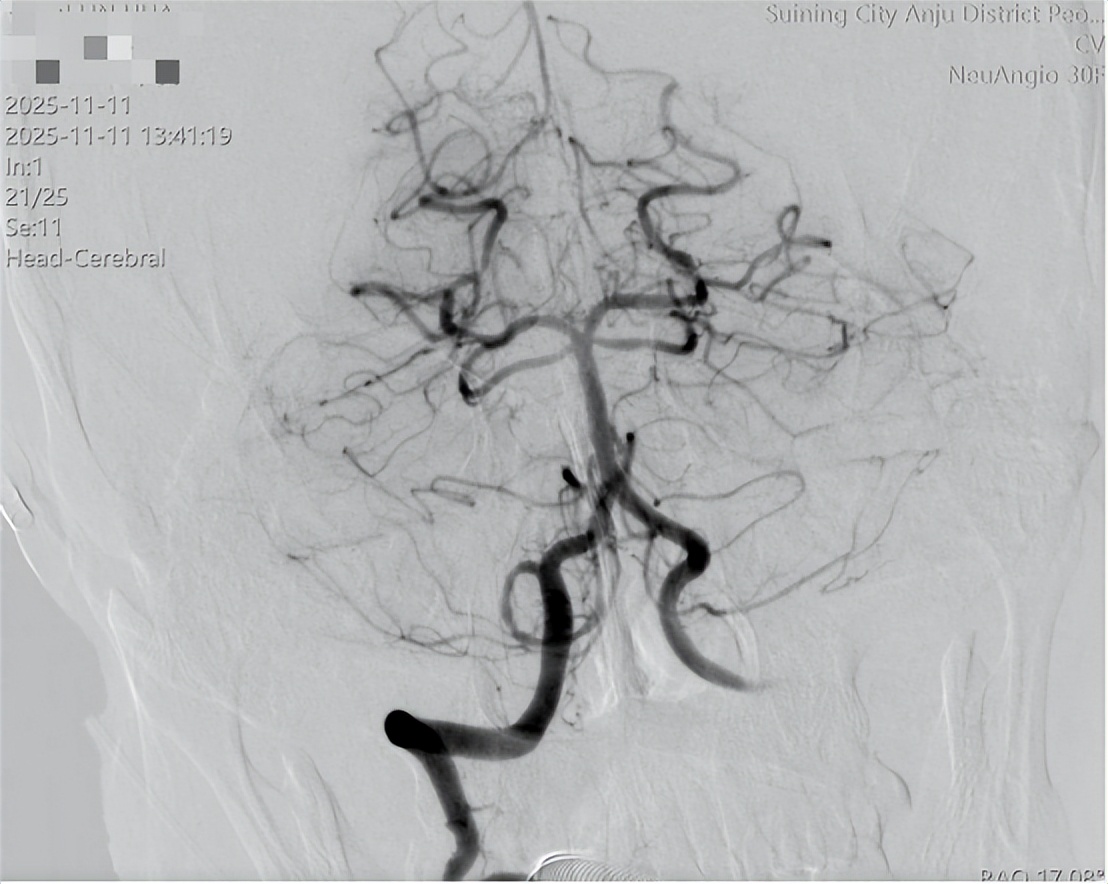

放射科紧急重启绿色通道,头颈部CTA检查结果证实——基底动脉闭塞!这是脑卒中里的“重症中的重症”,死亡率极高,必须立即进行动脉取栓手术。

12点26分,手术开始;12点54分,血栓成功清除!

廖家盛主任领衔的手术团队凭借精湛技术,在28分钟内打通堵塞的基底动脉,挽救了濒临坏死的脑组织。